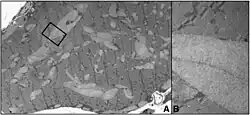

![]() | |

| A rendering of the human muscular form of phosphofructokinase. Mutations in the production of this enzyme are the cause of Tarui's disease.[3] The symmetry of the enzyme is a result of its tetrameric structure. | |